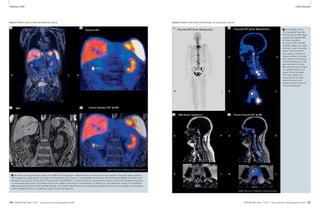

88 Whole-Body MR/PET Hybrid

Imaging: Technical

Considerations, Clinical

Workfl ow, and Initial Results

Harald H. Quick, et al.

88

Biograph mMR

Clinical mMR

102 Integrated Whole Body MR/PET

Imaging. First Examples of Clinical

Application

Alexander Drzezga, et al.